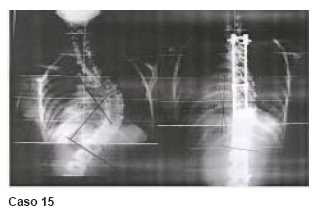

Las otras complicaciones detectadas fueron la ruptura de alambres distales en dos casos (4 y 5), que hemos subsanado mediante la colocación de tornillos pediculares en el último segmento caudal a artrodesiar, como se ve en la imagen posoperatoria del caso 10 y un caso de hiperestesia cutánea (caso 1). Esta complicación requiere analgésicos mayores durante 48 a 72 horas, cediendo luego espontáneamente.